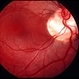

- nerve, optic nerve pit, visual field defect, Humphrey visual field, amblyopia, hemifield

- Kim Barrett C.O.A. Retina Specialist of Michigan, Grand Rapids, MI

Fundus camera

Optos California - Description

- A 14-year-old male presented with vision loss and VF defect. Patient was treated for presumed amblyopia with patching since age 4. He has had neurologic care for post traumatic skull fracture and brain bleed in 2012. Patient has a superior hemifield defect OS on HVF. IOP's WNL. There are vessels emanating from the optic pit OS. Patient is at risk of serous detachment. Current VA 20/20-2+2